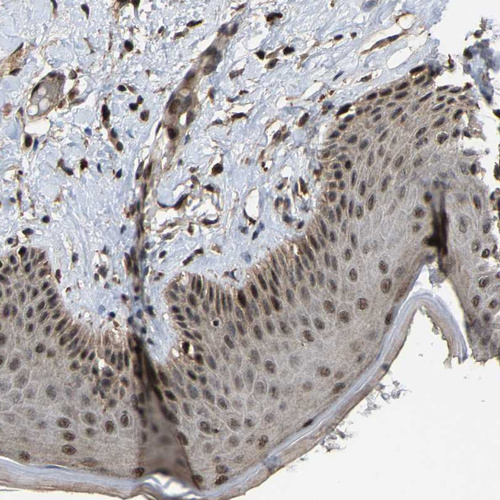

Immunohistochemical staining of human testis shows strong granular cytoplasmic positivity in cells in seminiferous ducts.